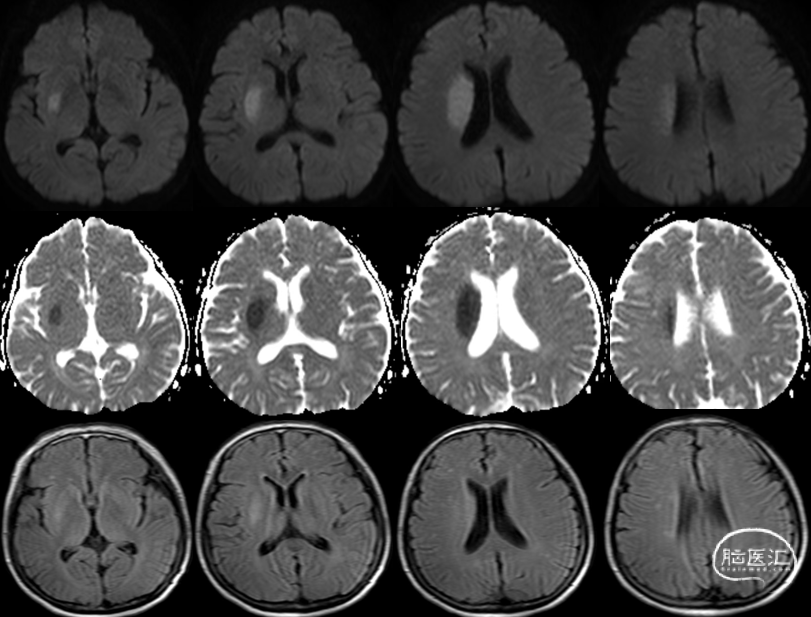

术前MRI

术前MRA:右侧大脑中动脉闭塞。

评估病变及代偿:Ⅰ型弓,右侧大脑中动脉闭塞,软脑膜动脉、大脑前动脉对其部分代偿,ASITN/SIR 2级。